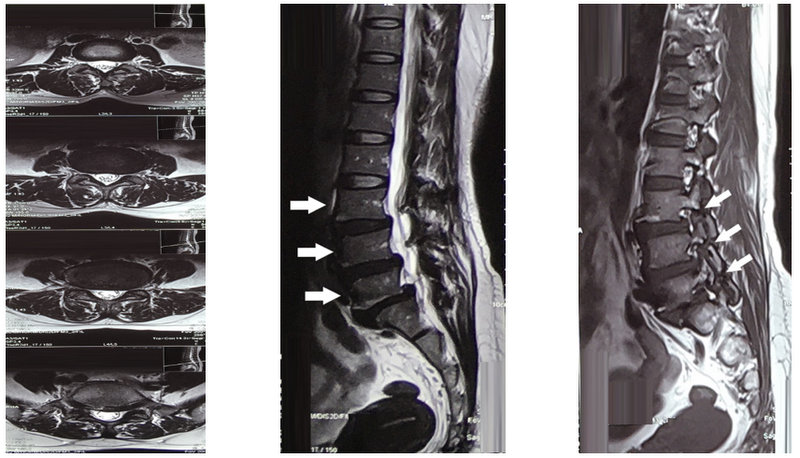

Hình 2. Cộng hưởng từ cột sống thắt lưng: Trái - mặt phẳng axial: phình đĩa đệm L5-S1 lệch trái chèn ép rễ thần kinh tương ứng Giữa – mặt phẳng sagittal: trượt đốt sống L3, L4, L5 ra trước độ I (mũi tên trắng). Hình Phải: khuyết eo đốt sống L3, L4, L5 (dấu mũi tên trắng)

Bệnh nhân nữ 49 tuổi vào viện vì đau thắt lưng âm ỉ trong hơn 8 tháng nay, gần đây triệu chứng đau tăng dần đặc biệt khi đứng và đi lại kèm co cứng vùng cột sống thắt lưng làm hạn chế vận động nhiều. Khám thực thể: đau dọc theo rễ thần kinh S1, điểm JOA và VAS cho đau thắt lưng là 8 và 10, dấu hiệu bậc thang dương tính, Lasègue dương tính 30 độ chân phải, 50 độ chân trái, X quang cột sống thắt lưng (Hình 1) và cộng hưởng từ cột sống thắt lưng cho thấy khuyết eo cột sống thắt lưng ba tầng ở L3-L5 với trượt nhẹ thân đốt sống L3, L4, L5 ra trước phối hợp phình lồi đĩa đệm ga chèn ép rễ thần kinh S1 hai bên trong ống sống (Hình 2) và thoái hóa đốt sống đĩa đệm đa tầng, đốt sống L3, L5, S1 thoái hóa MODIC II, biến dạng nhẹ đường cong sinh lý. Điều trị nội khoa bằng thuốc giảm đau, chống viêm, và giãn cơ không cải thiện. Bệnh nhân trượt đốt sống đa tầng do khuyết eo từ L3-L5 và có triệu chứng đau theo rễ thần kinh S1 nên chúng tôi đã quyết định tiến hành phẫu thuật PLIF: cố định cột sống bằng vít qua cuống tại L4-S1 và đặt mảnh ghép liên thân sống (PEEK) tại L5-S1.